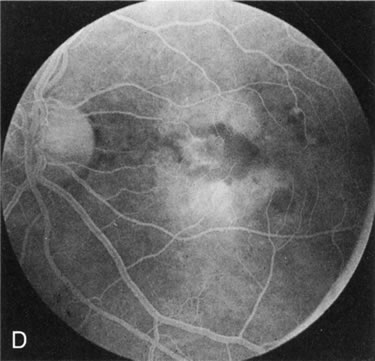

Of more clinical importance is the role of FA in the diagnosis and treatment of cystoid macular edema (CME) (Fig. 1C and D). Stereoscopic FA indicates that the leakage, which may be diffuse or have the typical petaloid stellate appearance of CME, can come from the perifoveal retinal capillaries, from the choroid through the RPE, or from a combination of both sources.4 With the recent suggestion that CME in RP may be successfully treated with acetazolamide,5, 6 FA is thus important to document the diagnosis of CME, establish the origin(s) of leakage, and follow patients during and after therapy.